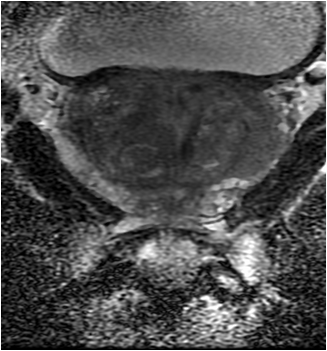

Figure 2 is biopsy proven prostate adenocarcinoma in a 62-year-old man with a Gleason grade of 6 (3+3). This example shows how functional imaging can help identify the tumor.

Figure 2b: Diffusion weighted image with ADC map shows a low ADC value in the left mid glaperipheral zone lesion (white arrow), indicative of prostate cancer.